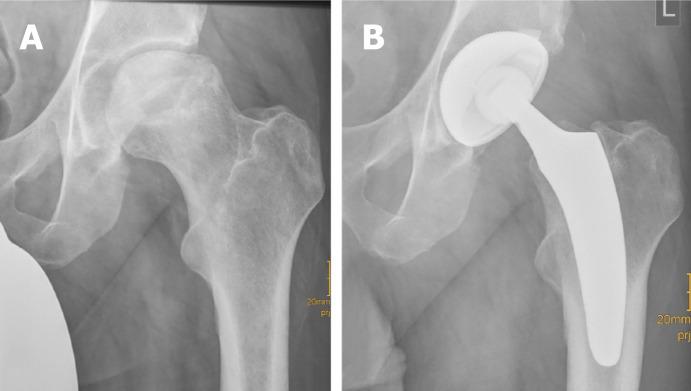

Short stems in total hip arthroplasty (THA) are becoming increasingly popular. In Germany, already 10.4% of all primary THAs are performed using a cementless short stem. The concept of modern, calcar-guided, short stems aims for an individualized reconstruction of the hip anatomy by following the calcar of the femoral neck, a bone- and soft-tissue-sparing implantation technique, and physiological loading. The stem design uses either metaphyseal fixation alone or additional diaphyseal anchoring, depending on the stem alignment and indication. These individualized anchorage types increase the potential indications for the safe use of a short stem. The design features may account for potential advantages of current short stem implants compared with earlier short-stem designs, particularly in cases of reduced bone quality or osteonecrosis of the femoral head and femoral neck fractures. The implantation technique, however, requires distinct knowledge regarding the characteristics of varus and valgus positioning, with the potential for clinical consequences. A learning curve for surgeons new to this technique must be taken into account. Cortical contact with the distal lateral cortex appears to be crucial to provide sufficient primary stability, and the use of intraoperative imaging to identify "undersizing" is highly recommended. Current results of several national registries indicate that calcar-guided short stems are among the most successful implants in terms of mid-term survivorship. However, long-term data remain scarce. This review introduces the characteristics of calcar-guided short-stem THA and summarizes the current evidence.